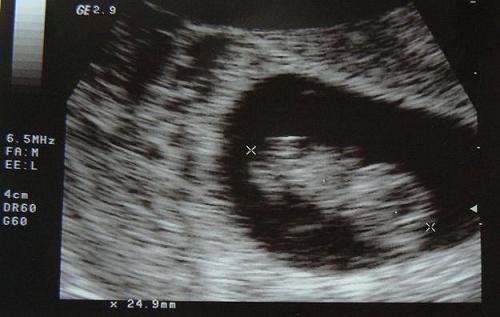

Kérdeztem, hogy vajon lehet-e már tudni a nemét, úgyhogy volt uh is. (Legközelebb lehet nem kérek, mert azért plusz pénz...)

Nagyon szégyenlős a pici, mindig elfordult... Mintha egy pillanatra látott volna valami lógót a lába között, de nagyon nem biztos. Én azért picit letörtem, mert nagyon kislányt szeretnék, azért még bízom benne...

De az a lényeg, hogy egészséges!

Szerinte akkor már tudni fogjuk a nemét.